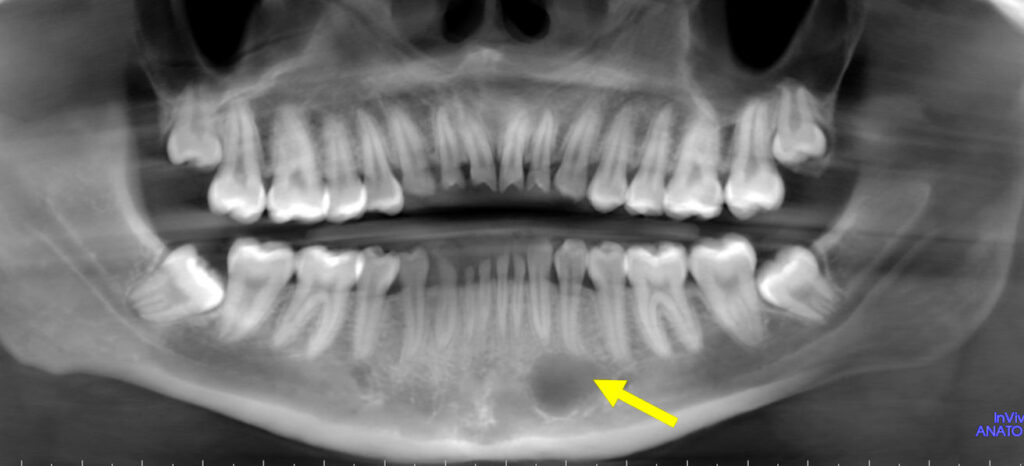

65-year-old man with mandibular growths

A 65-year-old man presented to the family dentist with multiple mandibular growths.

7-year-old girl with a radiographic finding

A 7-year-old girl with a radiolucent area on radiographs.